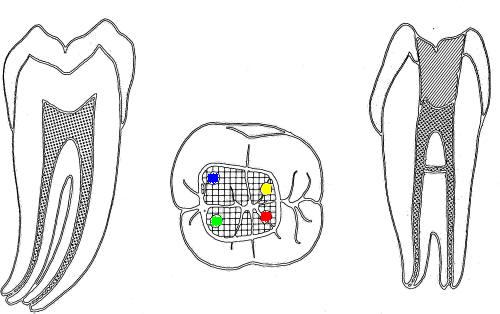

1º Molar Superior |

La flecha

amarilla indica un posible cuarto conducto. Debe

abrir hacia mesial para eliminar la pared

marcada en un circulo celeste, a la misma

profundidad que el conducto mesio-vestibular.

Ver imagen derecha. |

Entradas de los conductos que más frecuentemente

se hallan en los primeros molares superiores(1,2,23,27):

1º molar inferior (1,2,23,27)

En azul conducto mesio-vetibular

En verde conducto mesio-lingual

En rojo conducto distal

En amarillo un cuarto conducto,

si el conducto distal se encuentra desplazado hacia lingual,

existe una alta posibilidad de encontrar un cuarto conducto